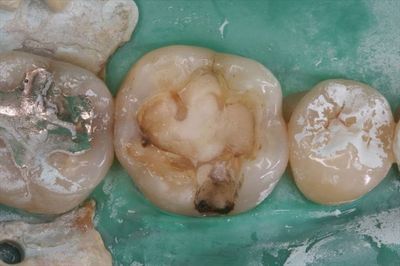

まずは金属を除去しました。

IMG_1400_R25.JPG

頬側溝部分の金属インレーの内面です。

多くのケースでこのようにすでに漏洩しています。